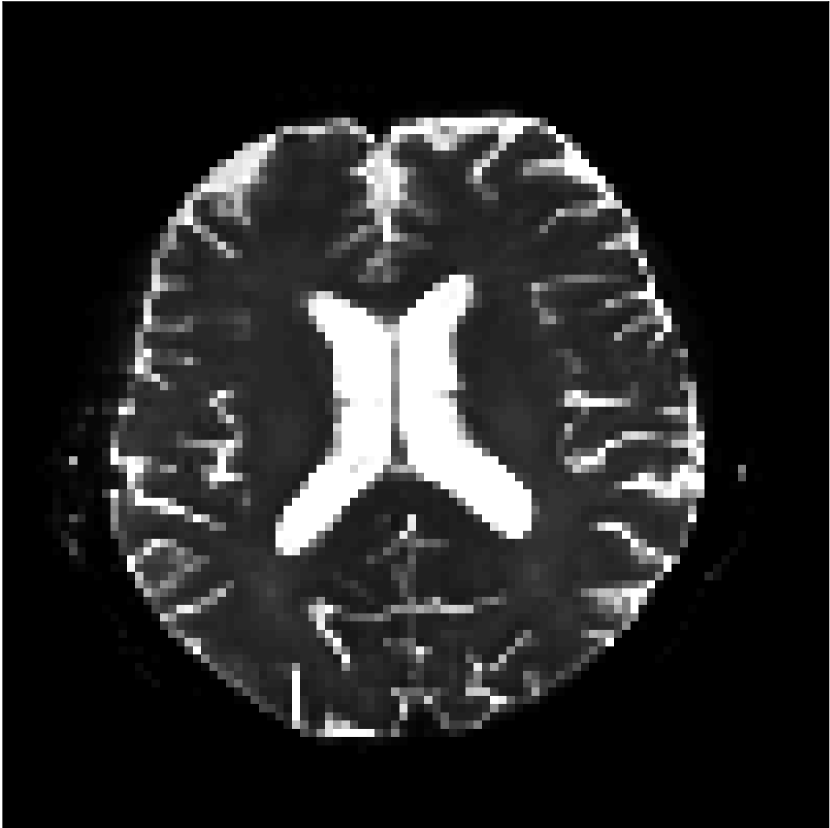

Figure 8 shows examples of non-diffusion-weighted images before and after processing. The raw images (Raw) served as the input for the magnitude deep learning (MCNN) and complex deep learning (CCNN) methods.

Raw 𝐱tsubscript𝐱𝑡\mathbf{x}_{t}

MCNN, fθ^(𝐱t)subscript𝑓^𝜃subscript𝐱𝑡f_{\hat{\theta}}\left(\mathbf{x}_{t}\right)

MCNN Resid., Ric(𝐱t)fθ^(𝐱t)Ricsubscript𝐱𝑡subscript𝑓^𝜃subscript𝐱𝑡\text{Ric}(\mathbf{x}_{t})-f_{\hat{\theta}}\left(\mathbf{x}_{t}\right)

CCNN, fθ^(𝐱t)subscript𝑓^𝜃subscript𝐱𝑡f_{\hat{\theta}}\left(\mathbf{x}_{t}\right)

CCNN Resid., Ric(𝐱t)fθ^(𝐱t)Ricsubscript𝐱𝑡subscript𝑓^𝜃subscript𝐱𝑡\text{Ric}(\mathbf{x}_{t})-f_{\hat{\theta}}\left(\mathbf{x}_{t}\right)

No PF

5/8 PF

Figure 8: Examples of non-diffusion-weighted images from in vivo data at b=0𝑏0b=0 s/mm2. Artifacts in the Raw image, 𝐱tsubscript𝐱𝑡\mathbf{x}_{t}, are corrected by the MCNN and CCNN models, fθ^(𝐱t)subscript𝑓^𝜃subscript𝐱𝑡f_{\hat{\theta}}(\mathbf{x}_{t}). Also shown are the residuals between the CNN corrections and the original Raw image with Rician bias correction Ric(𝐱t)Ricsubscript𝐱𝑡\text{Ric}(\mathbf{x}_{t}) [10]. The Gibbs artifacts removed by the methods are observed in the residuals. The MCNN method introduces some banding artifacts at the PF 5/8ths factor that are not present in the CCNN method.

Both methods remove artifacts, but the MCNN method allows residual rippling artifacts to pass through in the presence of partial Fourier. These rippling artifacts are not present in the CCNN method.